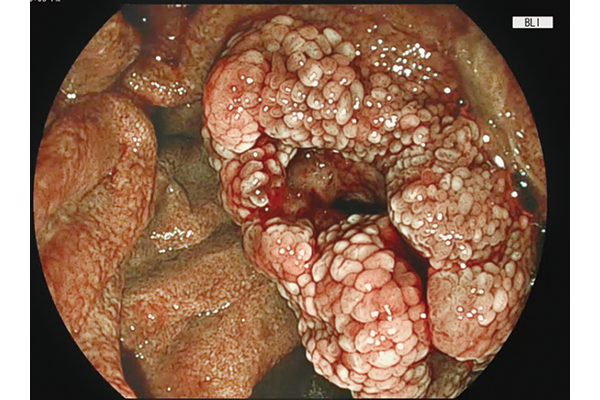

BLI,LCI and ACI technologies are incorporated.